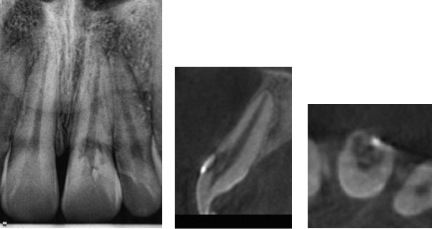

Cone Beam Computed Tomography (CBCT) Presentation

ECIR lesions can be difficult to appreciate in 2 dimensional radiographs so we usually take a cone beam CT scan of almost every ECIR case we encounter. The CBCT is invaluable as it allows for the most accurate 3 dimensional representation of the lesion and leads to more accurate assessment, diagnosis, and treatment planning (See Figure 9). Additionally, the scan provides an excellent visual aid for patient communication and education. We spend a lot of time getting to know every patient and we make sure they understand as much as possible. This is extremely important as many times ECIR lesions are asymptomatic and it may be difficult for a patient to understand the need for treatment when there is no pain. The truth is radiographic and CBCT images are invaluable for treatment planning however they are of very little value when it comes to predicting a patient’s discomfort.

Figure 9 – Radiograph of #9 with Class III lesion (left). CBCT coronal slice (center) and axial slice (right). CBCT reveals the lesion originated on the labial surface and extends into the coronal third of the root.